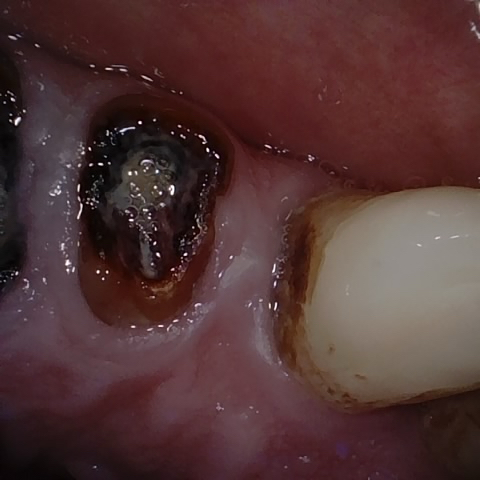

Annotated as "Good"